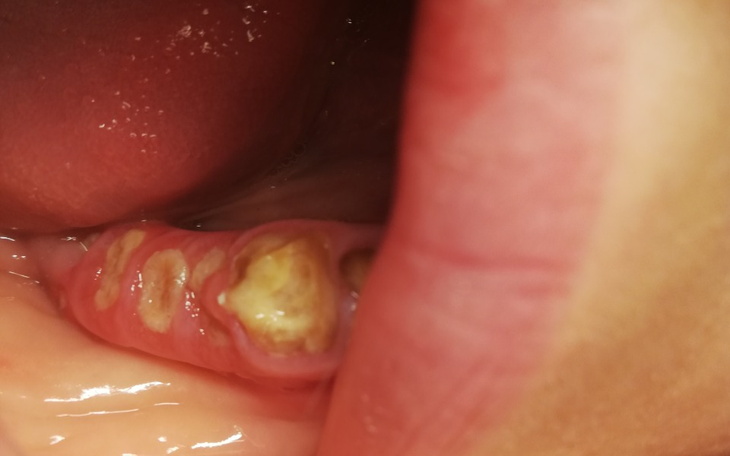

Trudno mi pisać o tym z czym się zmagam. Ciężko jest prosic o pomoc, ale zrobiłam już wszystko co mogłam. Mam naimie Magda, mam dwójkę kochających dzieci do których chciałabym się w końcu szczerze uśmiechnac..Prawie 70% osób mieszkających w Polsce, boryka się z przykrym problemem dotyczącym zębów - paradontozą. Warto wiedzieć, ze zapalenie przyzębia jest dziedziczne i niestety ja je odziedziczyłam. Koszt jest bardzo duży, a bez tego moje zęby dosłownie z dnia na dzień się kruszą, wypadają. Przy dwóch zębach urósł mi nadziąślak, który jest do usunięcia, co wiąże się z dodatkowymi kosztami.

Założyłam zbiórkę ponieważ każda złotówka się liczy i wierzę, ze z Wami uda mi się uzbierać potrzebna kwotę. Od jakiegoś czasu już nawet jedzenie sprawia mi problemy bo każda za twarda bułka, kotlet czy cokolwiek innego kruszy mi zęby, rano kiedy się budzę czuje okropny posmak w buzi połączony ze smakiem ropy, która zbiera mi się w zębach. Będę wdzięczna za każdą wpłacona złotówkę która spowoduje, ze w koncu będę mogła się usmiechac.